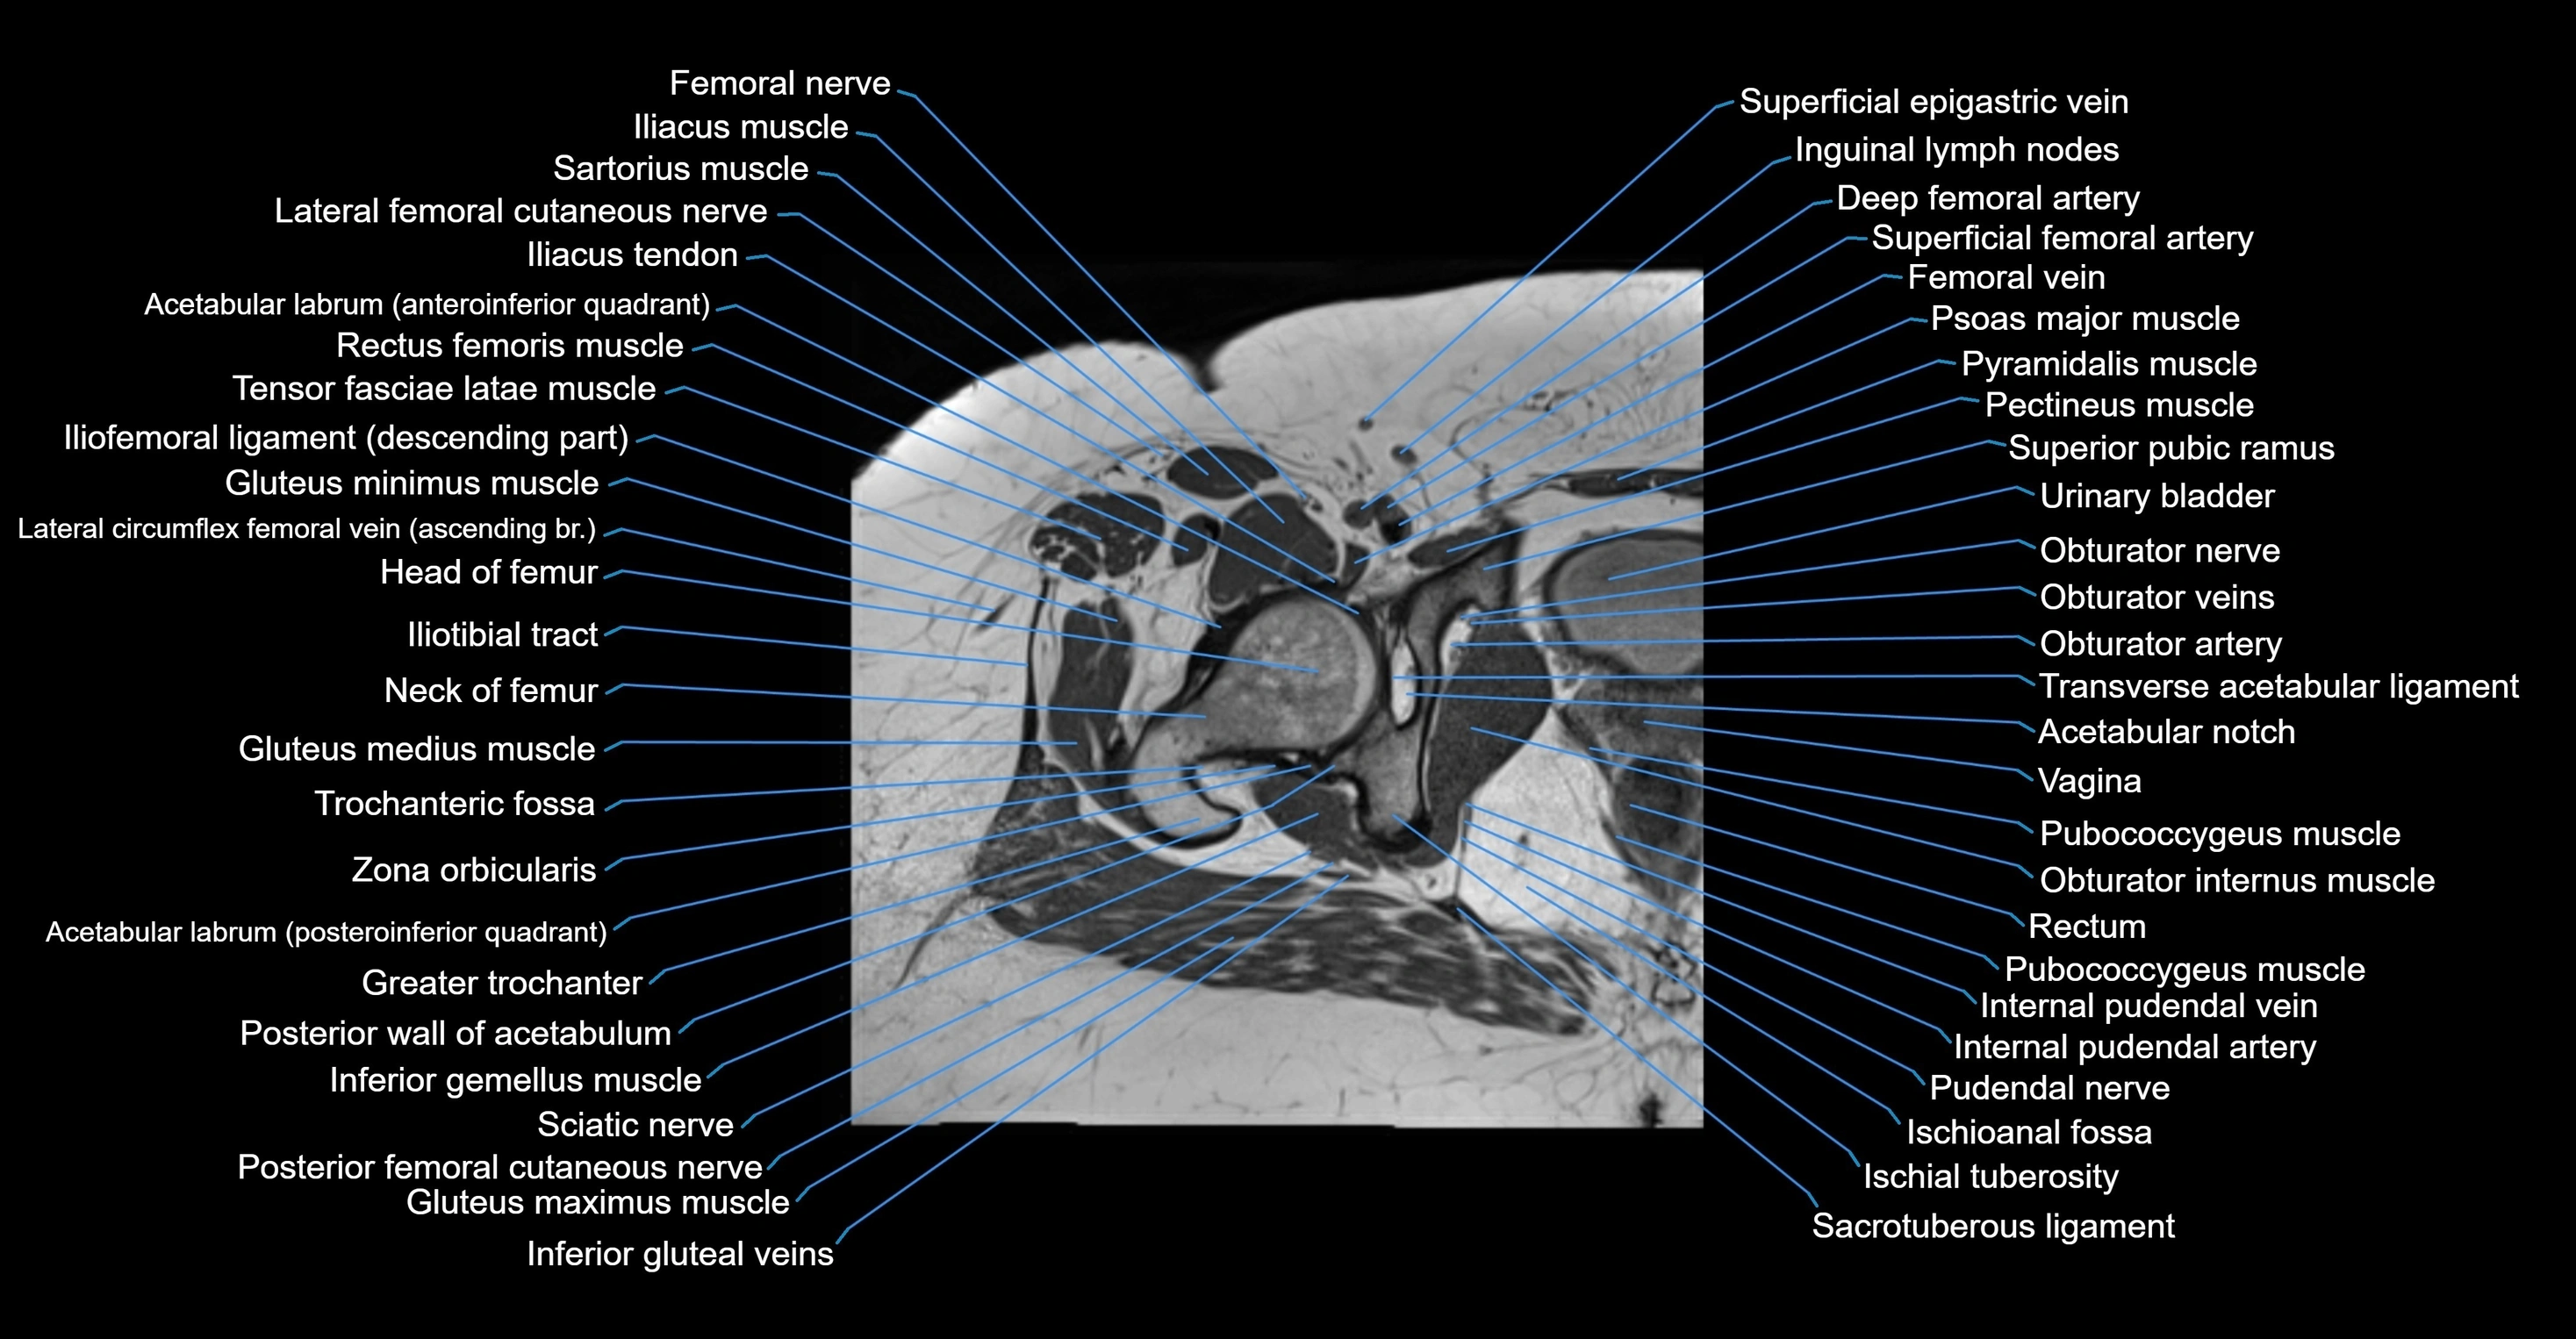

- Acetabular labrum

- Acetabular notch

- Femoral nerve

- Femoral vein

- Gluteus medius muscle

- Gluteus minimus muscle

- Greater trochanter

- Head of femur

- Iliofemoral ligament

- Iliopsoas muscle

- Iliopsoas tendon

- Iliotibial tract

- Inferior gemellus muscle

- Inguinal lymph nodes

- Ischial tuberosity

- Ischioanal fossa

- Levator ani muscle

- Neck of femur

- Obturator internus muscle

- Psoas major muscle

- Pubococcygeus muscle

- Pudendal nerve

- Pyramidal muscle (pyramidalis muscle)

- Quadratus femoris muscle

- Rectus femoris muscle

- Sacrotuberous ligament

- Sartorius muscle

- Superficial femoral artery

- Superior pubic ramus

- Tensor fasciae latae muscle

- Transverse acetabular ligament

- Trochanteric fossa

- Urinary bladder

- Vagina

- Zona orbicularis ligament